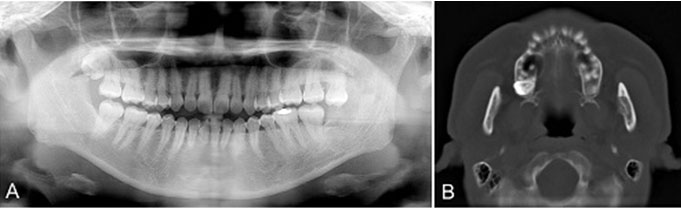

At present, three years and six months have passed since the operation, panoramic X-ray and CT showed increased radiopacity and bone regrowth, and the postoperative course has been uneventful without recurrence (Figure 5 and Figure 6).

Figure 5: Panoramic X-ray and CT images at three years and six months postoperatively. (A) Bone regrowth is observed. (B) Increased radiopacity due to new bone formation is observed.